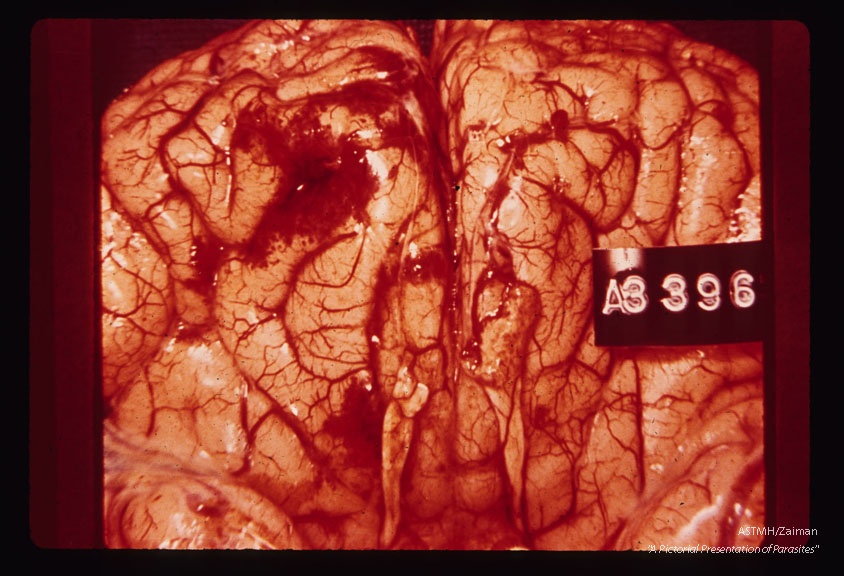

Lee case of primary amoebic meningoencephalitis. Whole brain.

Naegleria

Description: Lee case of primary amoebic meningoencephalitis. Whole brain.